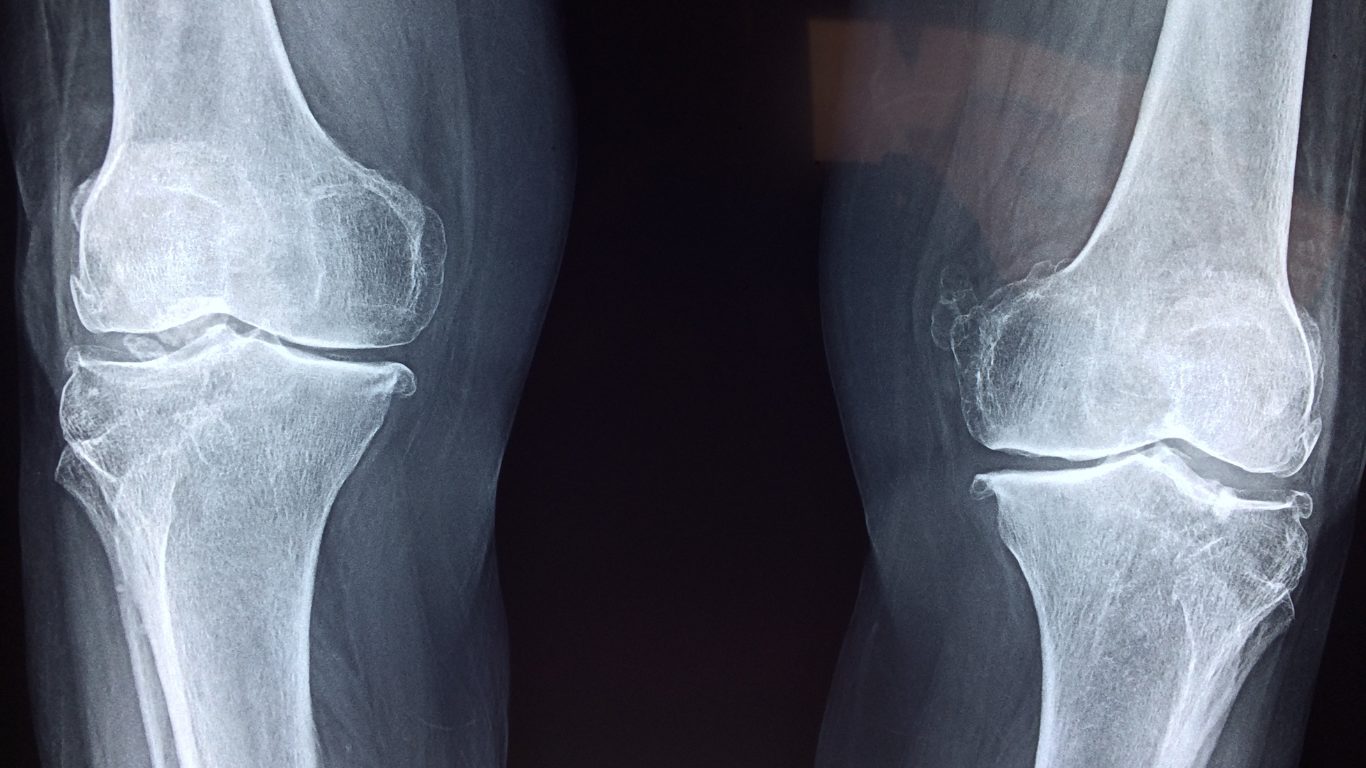

膝に水が溜まることを「関節水腫」と呼ばれます。関節の中には"関節包"という関節を包む丈夫な袋状の組織があり、関節水腫はその関節包の中に通常より多くの関節液が溜まっている状態です。これは関節液を生成する滑膜に炎症が起き、分泌と回収のバランスが崩れることで起こります。主な原因としては、「変形性関節症」や「半月板損傷」などがあげられます。水が溜まる関節水腫の患者数を指す直接的なデータは現在見つかりませんが、原因とされる変形性膝関節症は【#6】でも記したように約2,500万人もの患者数が現在いるとされています。これほどの患者数がいて、臨床数(治療実績)も十分にあるにも関わらず改善した方がみられないのはどうしてでしょうか。きっとみなさんの親族・友人・知人の中で「関節水腫」の方、治療を繰り返すが中々改善が見込めない方がいるのではないでしょうか。

上記文では、関節水腫の主な原因として「変形性膝関節症」や「半月板損傷」などと述べておりますが、これは一般的に整形外科などで言われる見解、ネットで検索して表示されるものとしてご紹介を致しました。一方、姿勢科学的な視点からこの問題を捉えた場合の考え方をご紹介いたします。まず水が溜まる仕組みを詳しく説くと、そもそも膝は上から大腿骨と脛骨、そして中間に膝のお皿と言われる膝蓋骨の主に3つの骨から構成されています。膝は上半身の体重を支える為に丈夫で安定しておく必要があります。その為、大腿骨の末端は丸みを帯びた1点ではなく、2点に分かれて隆起しており力を分散するような構造となっております。【#6】で記したように、膝は安定且つしなやかさも必要とする非常に矛盾した部位になっており、屈曲伸展をスムーズに繰り返すことで快適な歩行を可能にしているのです。

屈曲伸展をスムーズにしている部位に大きな負荷がかかる訳なので、ちょっと姿勢が傾くことで重心バランスが左右乱れて関節のかみ合いが上手くいかず、半月板(軟骨組織)が薄れて骨同士が干渉してやがて変形していきます。その際に、動かしにくくなった膝をスムーズに動かそうと体内で生産された潤滑液(ヒアルロン酸)を膝に流し込むのです。これは、けがをしたら自然に治癒する力や運動をすると心拍数を上げて血液循環を加速させることなどと同じように、人間が生まれながらに持つ本能的な作用です。しかし、関節包や潤滑液不足で動かなくなった訳ではないので、そこに液が流れてきても関節は動かないので溜まる一方です。この状態が「関節水腫」なのです。